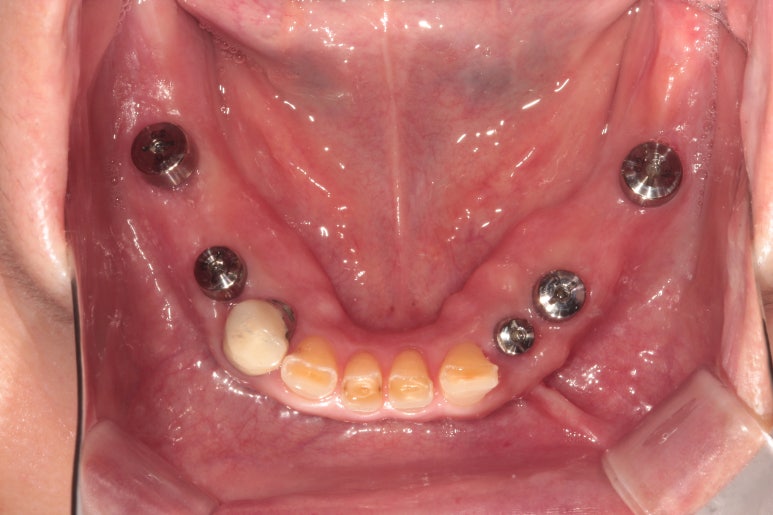

딱 2주일만 지나도 이렇게 깔끔하게 낫는답니다.

각화치은의 양이 증대되어 양치질 하기에 좋은 환경이 조성되었어요!

이러한 상태에서 맞춤형 지대주와 임시치아를 접착하여 아래 틀니를 쓰지 않아도 되게끔 해드렸습니다.

위턱 임플란트 수술 후 3개월의 치유기간을 거친 후 임플란트 2차 수술을 했습니다.

위 임플란트들도 뚜껑이 생긴 것을 보실 수 있으실거에요.

치유지대주를 연결해 주었습니다.